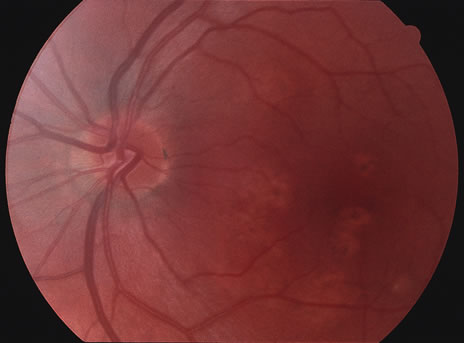

Fundus Findings.

Classically, there are broad areas of chorioretinal atrophy that may take a jigsaw pattern. Usually the atrophy is centered on the disc and spreads along the vascular arcades and then towards the fovea. Sometimes the choroiditis starts within the macula and spreads out from there. Both eyes tend to be affected although there may be marked asymmetry between the two eyes. The active disease appears as yellow-gray areas. If there is evidence of previous disease, then the active areas tend to be at the edge of the chorioretinal atrophy (Figs. 16 to 18). Rarely, there may be several noncontiguous areas of chorioretinal atrophy in the eyes. Retinal vasculitis at the site of an active lesion and retinal vein occlusions may rarely be seen.

Fig. 16. A. Color fundus photograph showing the jigsaw pattern of choroidal and retinal atrophy extending from the disc along the arcades. At the inferior edge of the superotemporal lesion there is a recurrence noted by the grayness of the retina. B. Fluorescein angiogram in the laminar venous phase showing a large window defect in the area of inactive choroiditis and blockage of the choroidal fluorescence in the area of active choroiditis. C. In the late phase of the fluorescein angiogram there is staining of the edges of the inactive choroiditis and marked hyperfluorescence in the area of active choroiditis.